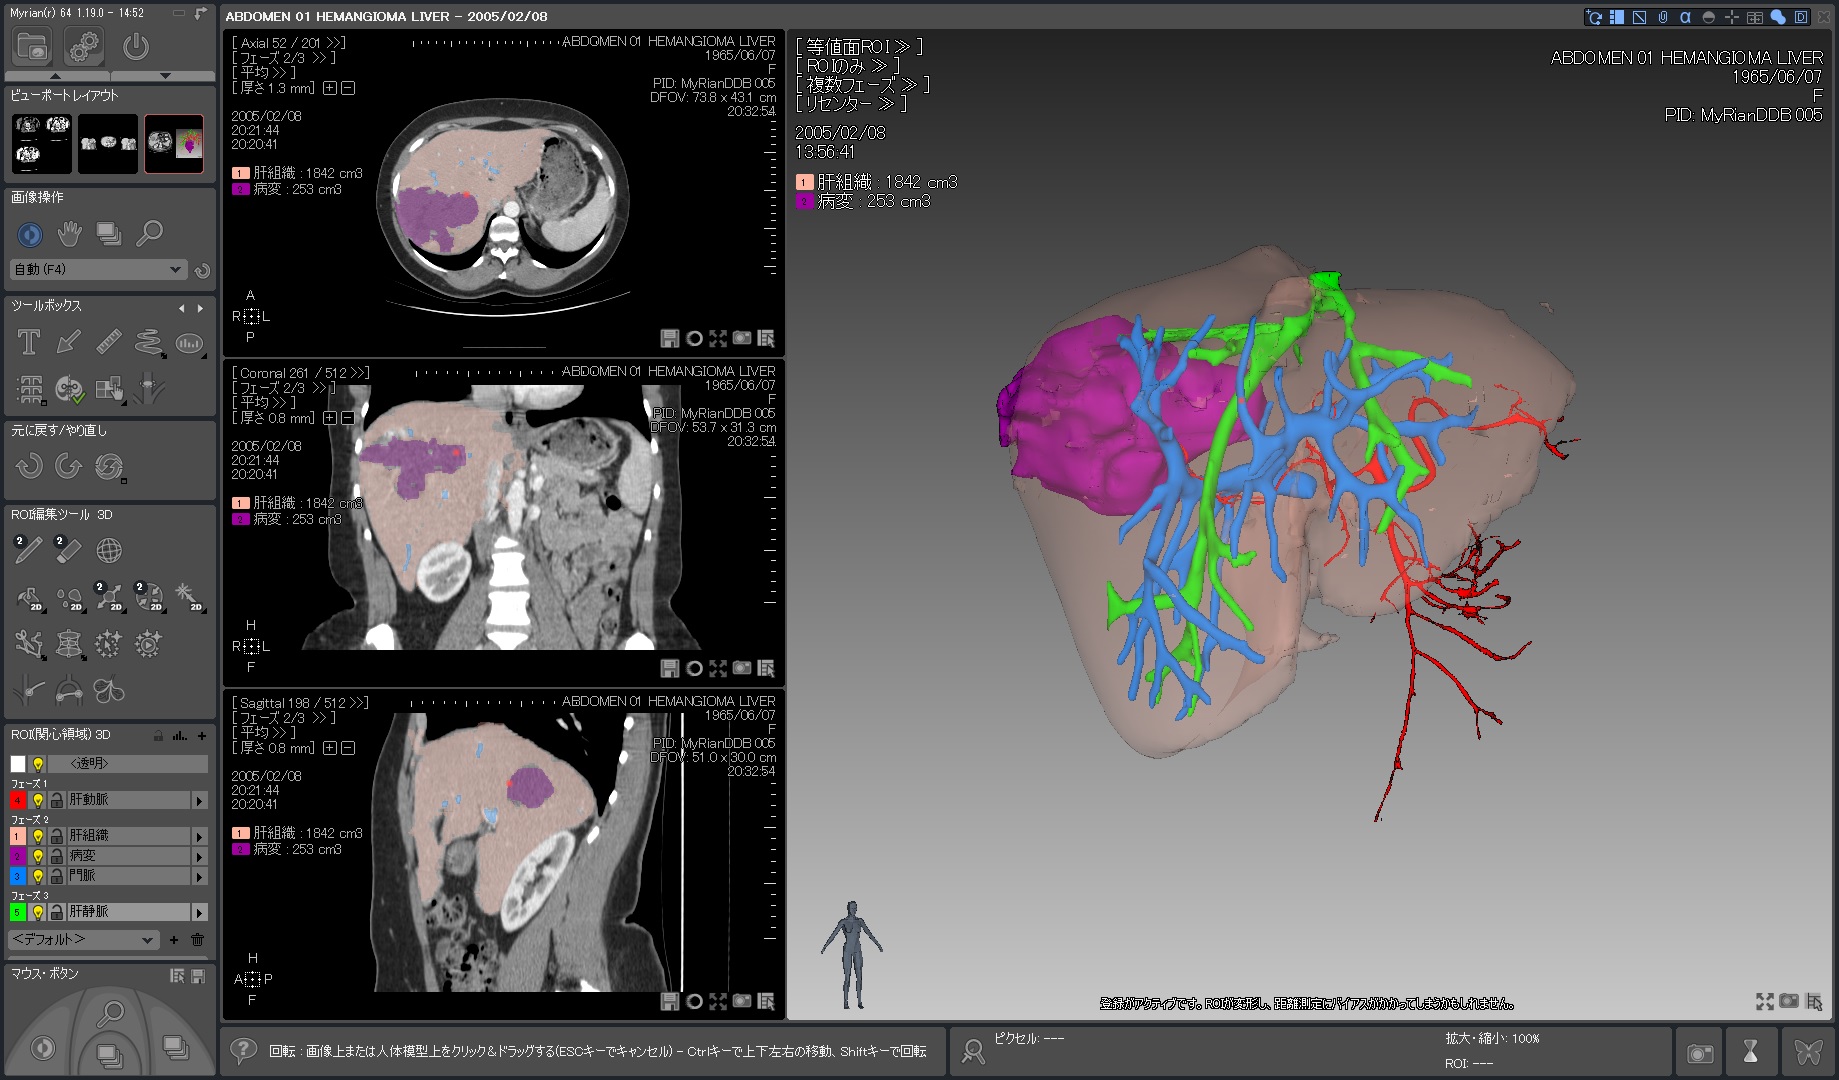

Myrian®XP-Liver 肝臓アプリケーション

世界的な実績と評価を得ている、肝臓解析と手術計画用ソフトウェア

独自に開発された、正確な非剛体レジストレーションと優れたセグメンテーション・アルゴリズムにより肝血管系、肝実質、腫瘍などを数秒で抽出します。

3D PDFによる立体表示ではコミュニケーションの向上に寄与するでしょう。

当製品は3D業界の先駆けとして、世界トップの施設で使用されています。

| 1.病変部領域 正常部領域の ワンクリック セグメンテーションと 体積表示 |

|

|---|---|

| 2.肝臓血管系の半自動抽出 |  |

| 3.血管支配域の表示 |  |